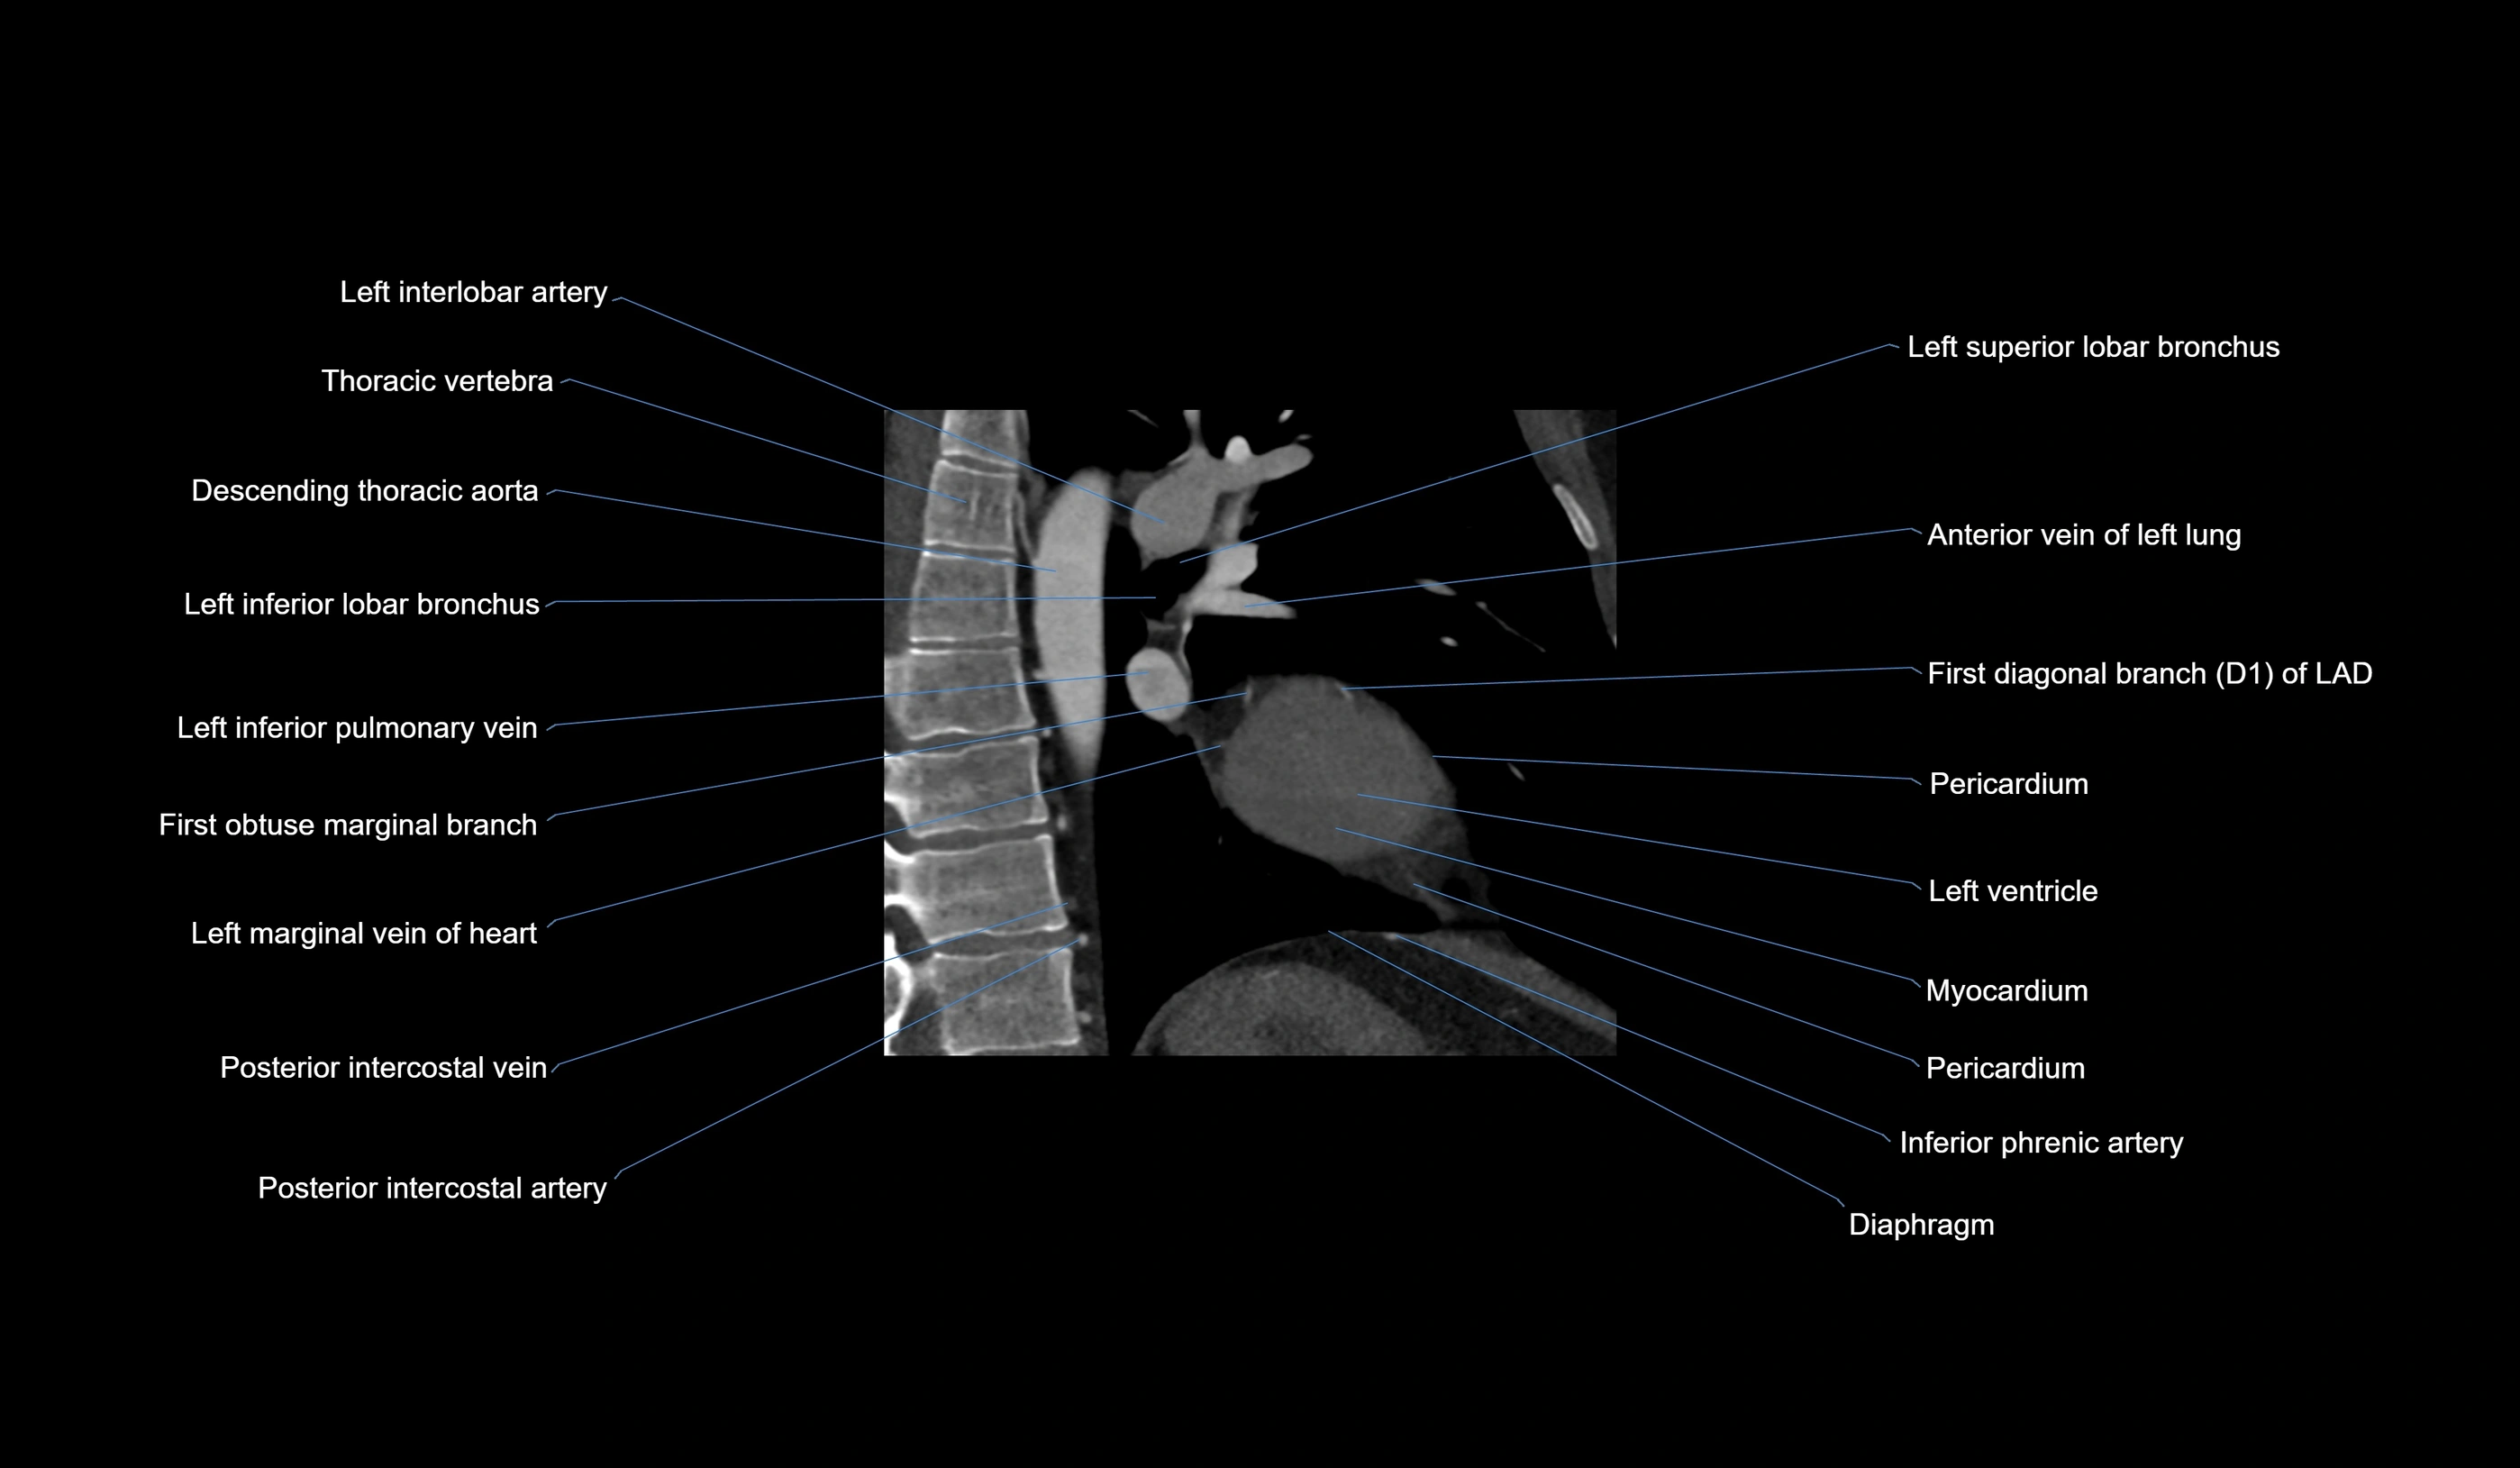

- Acute marginal artery (AM)

CT Appearance

CT Coronary Angiography (CCTA):

-

Best non-invasive modality for acute marginal artery visualization

Shows origin, course along the acute margin, and right ventricular branches

Detects stenosis, occlusion, calcified and non-calcified plaques, aneurysm, or anomalous course

Multiplanar reformats and 3D reconstructions help in pre-PCI and surgical planning

Critical for assessing right ventricular infarction risk in RCA disease

CT images